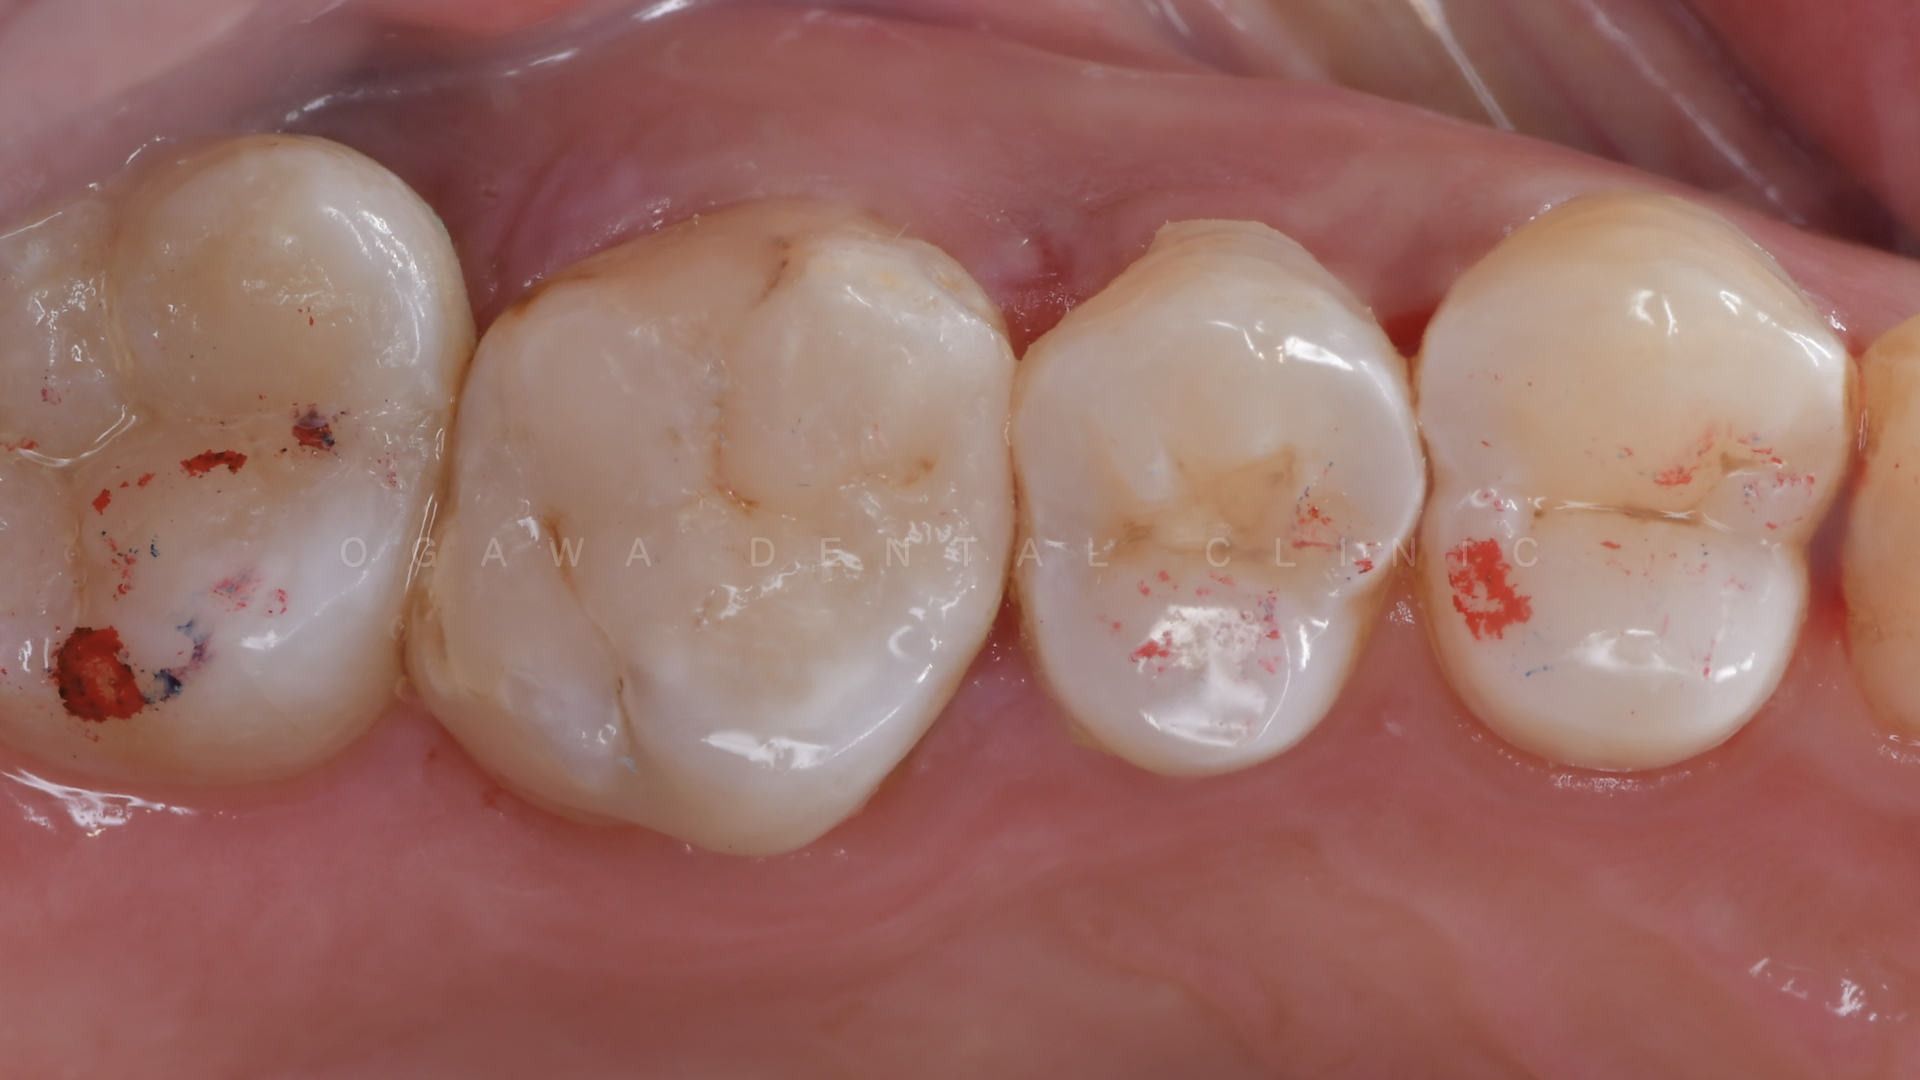

ダイレクトボンディングとは、虫歯を完全除去した後に、歯科用の高品質な樹脂(レジン)を歯に直接盛り足し、形や色を丁寧に整える治療法です。

天然歯のような色調や形態を再現でき、歯を大きく削らずに見た目を改善できるのが大きな特徴です。

複数の色調のレジンを重ねて塗り分け、天然の歯のようなグラデーションと形態を再現します。 - 将来的な修正も可能

ダイレクトボンディングは、「できるだけ削らず、美しく」を叶える審美的・低侵襲治療です。